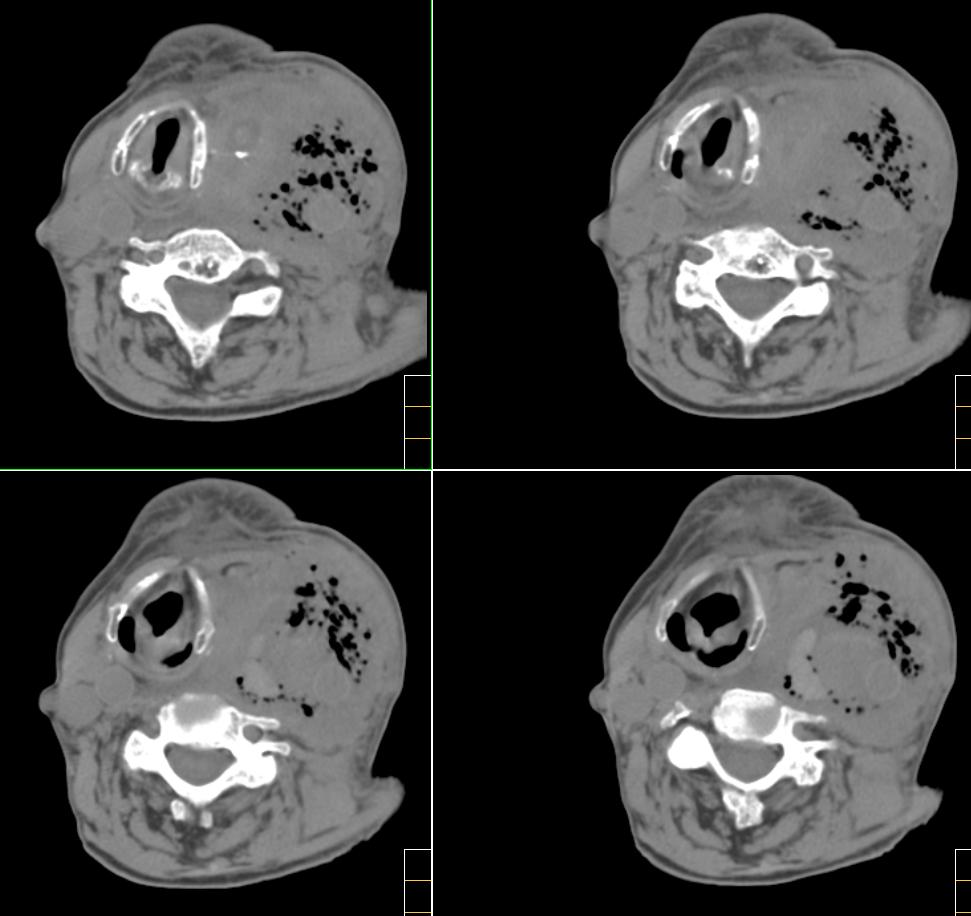

f、72y,左侧颈部发现包块及疼痛1周,彩超提示颈部血管破裂?

左颈部血管增粗,周围软组织肿胀模糊,内有蜂窝状积气影,左侧甲状腺增大,气管受压右移,气管软骨环未受侵。结合病史较短考虑:左颈部脓肿破裂并血管瘤形成,左甲状腺瘤。